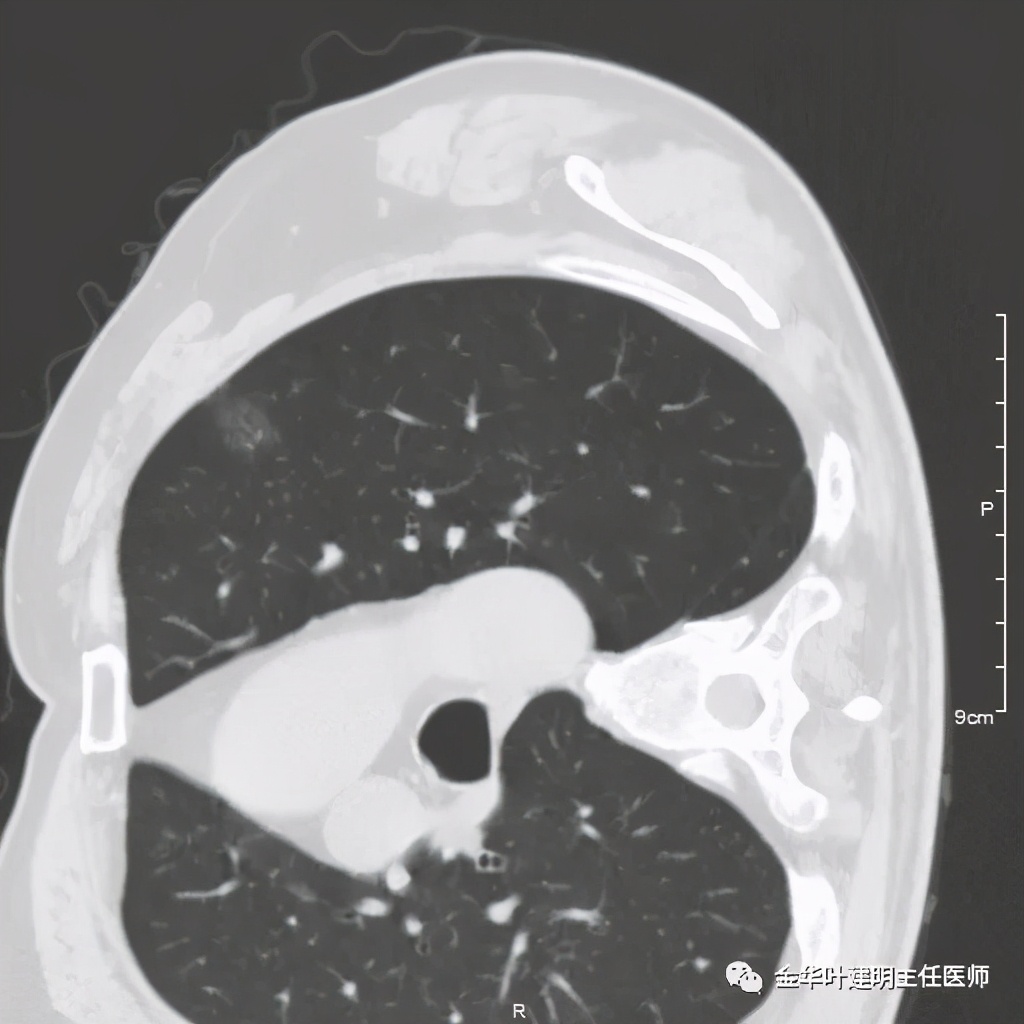

三、浸润性腺癌腺泡型:

影像特征:浸润性腺癌腺泡型的表现,已经是较为典型的恶性,整体上基本是实性密度,但腺泡型的腺癌,其收缩力弱,胸膜凹陷或毛刺征少见,最主要的特点是 密度不均的实性结节 ,边缘可略模糊,但整体病灶的轮廓比较清楚,感觉在正常肺组织区域比较突兀的出现一个实性病灶,缺乏平常认为的空洞、毛刺、分叶、牵拉等典型肺癌的影像征。此型有时与慢性炎或肉芽肿可能会不易区分,适当抗炎治疗后复查对比可能是可以选择的方案之一。